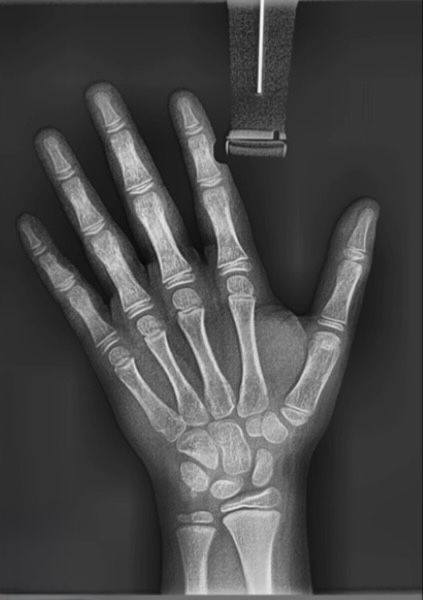

Raio x de mão e unho (carpal)

Exame que avalia a maturidade óssea por meio da análise da mão e punho, auxiliando no planejamento ortodôntico e verificando estagio de crescimento.